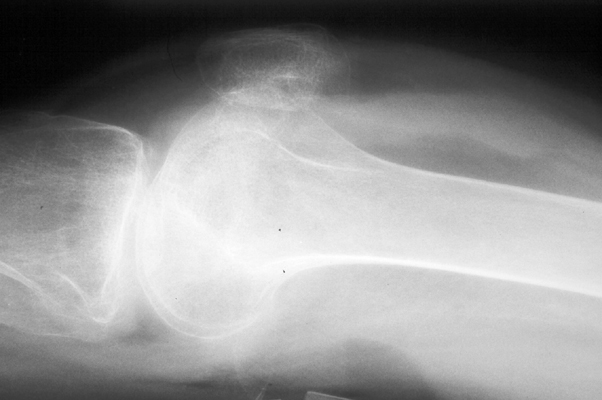

Lipohemarthrosis

Fat fluid interface seen on the multiple lateral radiographs of the knee secondary to lipohemarthrosis. The fat-blood interface (FBI) is a very suggestive sign of underlying fracture extending into the joint. If no fracture is readily identified, diligent search should be undertaken.

Cross table lateral knee - Click on the image for a larger versionACross table lateral - Click on the image for a larger versionB